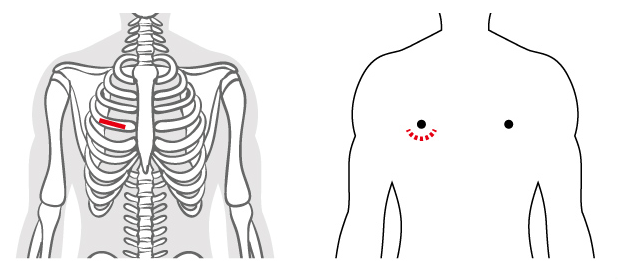

MICS(ミックス)とは、大きな胸骨正中切開で行う心臓手術を小さな切開で行う心臓手術のことで、英語の略語からMICS(ミックス)と呼ばれています。具体的には腋の下もしくは乳房の下を5-7cm切開して肋骨の隙間より心臓の手術を行います。MICS(ミックス)では、胸骨を切らないため、出血が少なく、傷の感染のリスクもほとんどありません。また、一般的に胸骨正中切開の手術後は、自動車、自転車の運転や上半身を使う肉体労働や、テニスやゴルフなどのスポーツは、約2ヶ月間は控える必要があります。そのため多くの患者さんが2ヶ月間のうちに体力が低下し、結局、日常生活に戻るのに数ヶ月-半年かかることもあります。ミックス手術ではそのような運動制限がないため、早期リハビリが可能となり、早期社会復帰が可能になります。 傷が小さく美容面にも大変優れており、特に女性では、傷口が乳房に隠れる、ほとんど見えなくなるため、非常に満足度の高い手術です。

従来の心臓手術

MICS(小切開心臓手術)